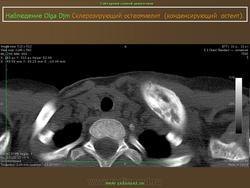

Синонимы - Stieda (Штида) (Штиды) - Albers-Schonberg (Альберс-Шенберга) болезнь - Кость пятнистая - Остеопатия врожденная пятнистая множественная - Остеопатия врожденная рассеянная склерозирующая - Остеопатия диссеминированная конденсирующая - Остеопойкилия - Остеопойкилоз - Штиды (Штида) (Stieda) - Альберс-Шенберга (Albers-Schonberg) болезнь Характеристика Врожденное нарушение развития костей. Клинически не проявляется. Случайная рентгенологическая находка. Рентгенологическая картина Множественные мелкие и крупные (до 10 мм) очаги остеосклероза округлой или овальной формы, расположенные в эпифизах трубчатых костей, а также в других костях, за исключением ключицы.

Остит генерализованный конденсирующий

Характеристика

Врожденное нарушение развития костей. Клинически не проявляется. Случайная рентгенологическая находка.

Рентгенологическая картина

Множественные мелкие и крупные (до 10 мм) очаги остеосклероза округлой или овальной формы, расположенные в эпифизах трубчатых костей, а также в других костях, за исключением ключицы.